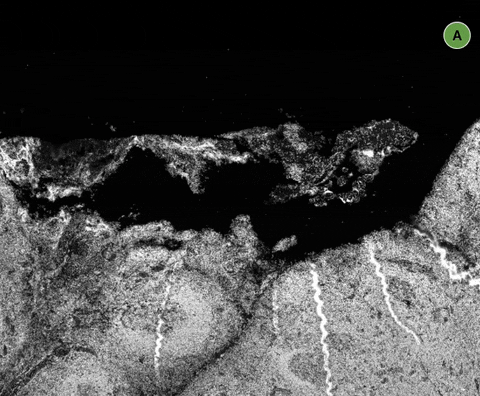

Below that, we have our scale:

We know how large your image is from its metadata, and that means we can display an accurate scale at all times, rounded to a pleasant number to deal with. (Our sample image here is about 1.3cm wide).